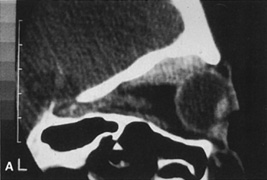

In the case of more deeply placed superior orbital lesions, it is possible to use an air drill to burr away the superior orbital rim to provide better exposure and allow deeper access in the superior orbit (Fig. 24). Because the contour of the brow is established by the supraorbital ridge, fairly extensive removal of the superior orbital rim can be carried out without cosmetic deficiency. However, care must be taken to identify the supraorbital nerve and avoid damage to it during this maneuver, or hypesthesia over the forehead and scalp can result. The amount of bone removal also is limited by the degree of pneumatization of the overlying frontal sinuses, although inadvertent entry into the sinus usually is not a problem as long as the nasofrontal duct is not compromised.

Fig. 24. A. Sagittal CT scan of a lesion in the peripheral superior orbit behind the equator of the globe. B. Lid crease incision and superior dissection are used to expose the superior orbital rim. C. The superior orbital rim then can be burred away to provide greater access to the more posterior orbital lesion.